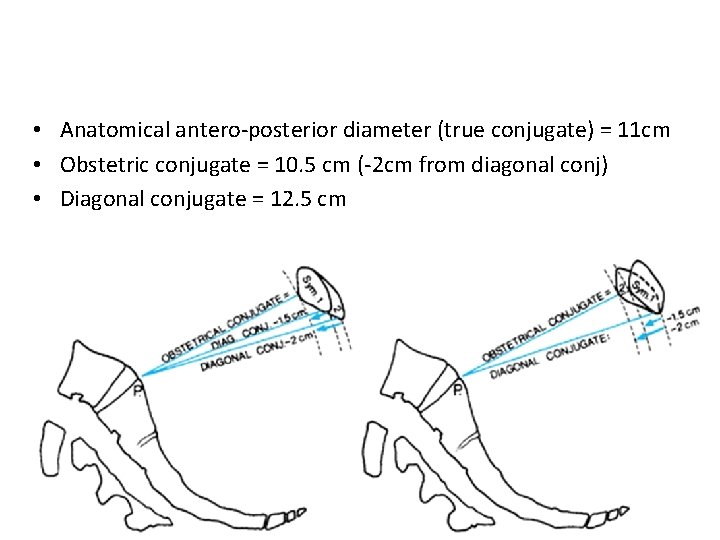

• Anatomical antero-posterior diameter (true conjugate) = 11 cm • Obstetric conjugate = 10. 5 cm (-2 cm from diagonal conj) • Diagonal conjugate = 12. 5 cm